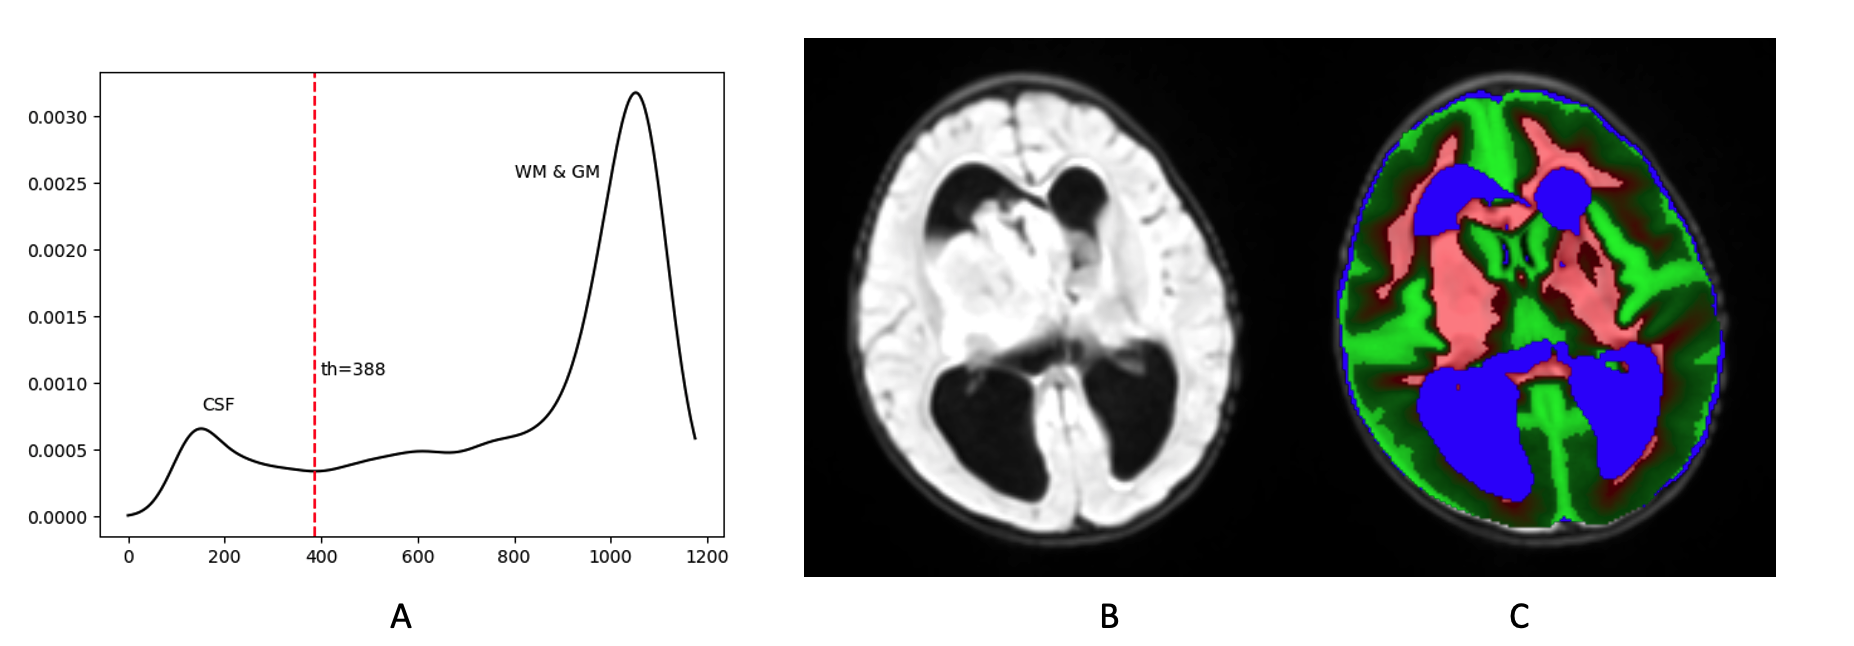

The WM and GM probabilities are initialized as ICBM atlas priors (affine transformed into the native space) using Advanced Normalization Tools (ANTs [2]). Due to abnormal distributions of CSF (e.g., hydrocephalus) common in brain tumor patients, CSF probability is not initialized as the ICBM atlas prior. Our model assumes CSF to be darkest component/peak among all tissue types under consideration in FLAIR. Figure 1A shows an example histogram from a representative patient with ATRT. The left most peak is CSF and the right most peak is a mixture of WM and GM. The red dotted line is used as the threshold (th𝑡th) for CSF prior estimation, which is determined by the local minima on the right side of the CSF peak. Voxels of intensity value lower than th𝑡th are initialized as Pr(CSF)=0.9PrCSF0.9\Pr(\mathrm{CSF})=0.9.

Refer to caption

Figure 1: An example of prior probability estimation on an ATRT case. A) Estimated probability density function of FLAIR using KDE. B) FLAIR image. C) Estimated prior probabilities of WM (red), GM (green) and CSF (blue).